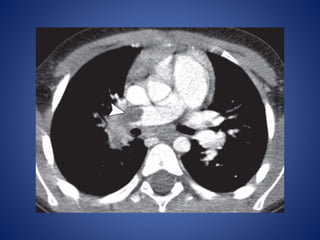

• #40 Adrenal cortical carcinoma in a 5-year-old girl. Post-contrast: large left retroperitoneal mass (arrow) with central necrosis (*). Tumor thrombus (arrowhead) is seen in the inferior vena cava

• #41 Axial chest CT image demonstrates a pulmonary embolus (arrowhead) in the right pulmonary artery.